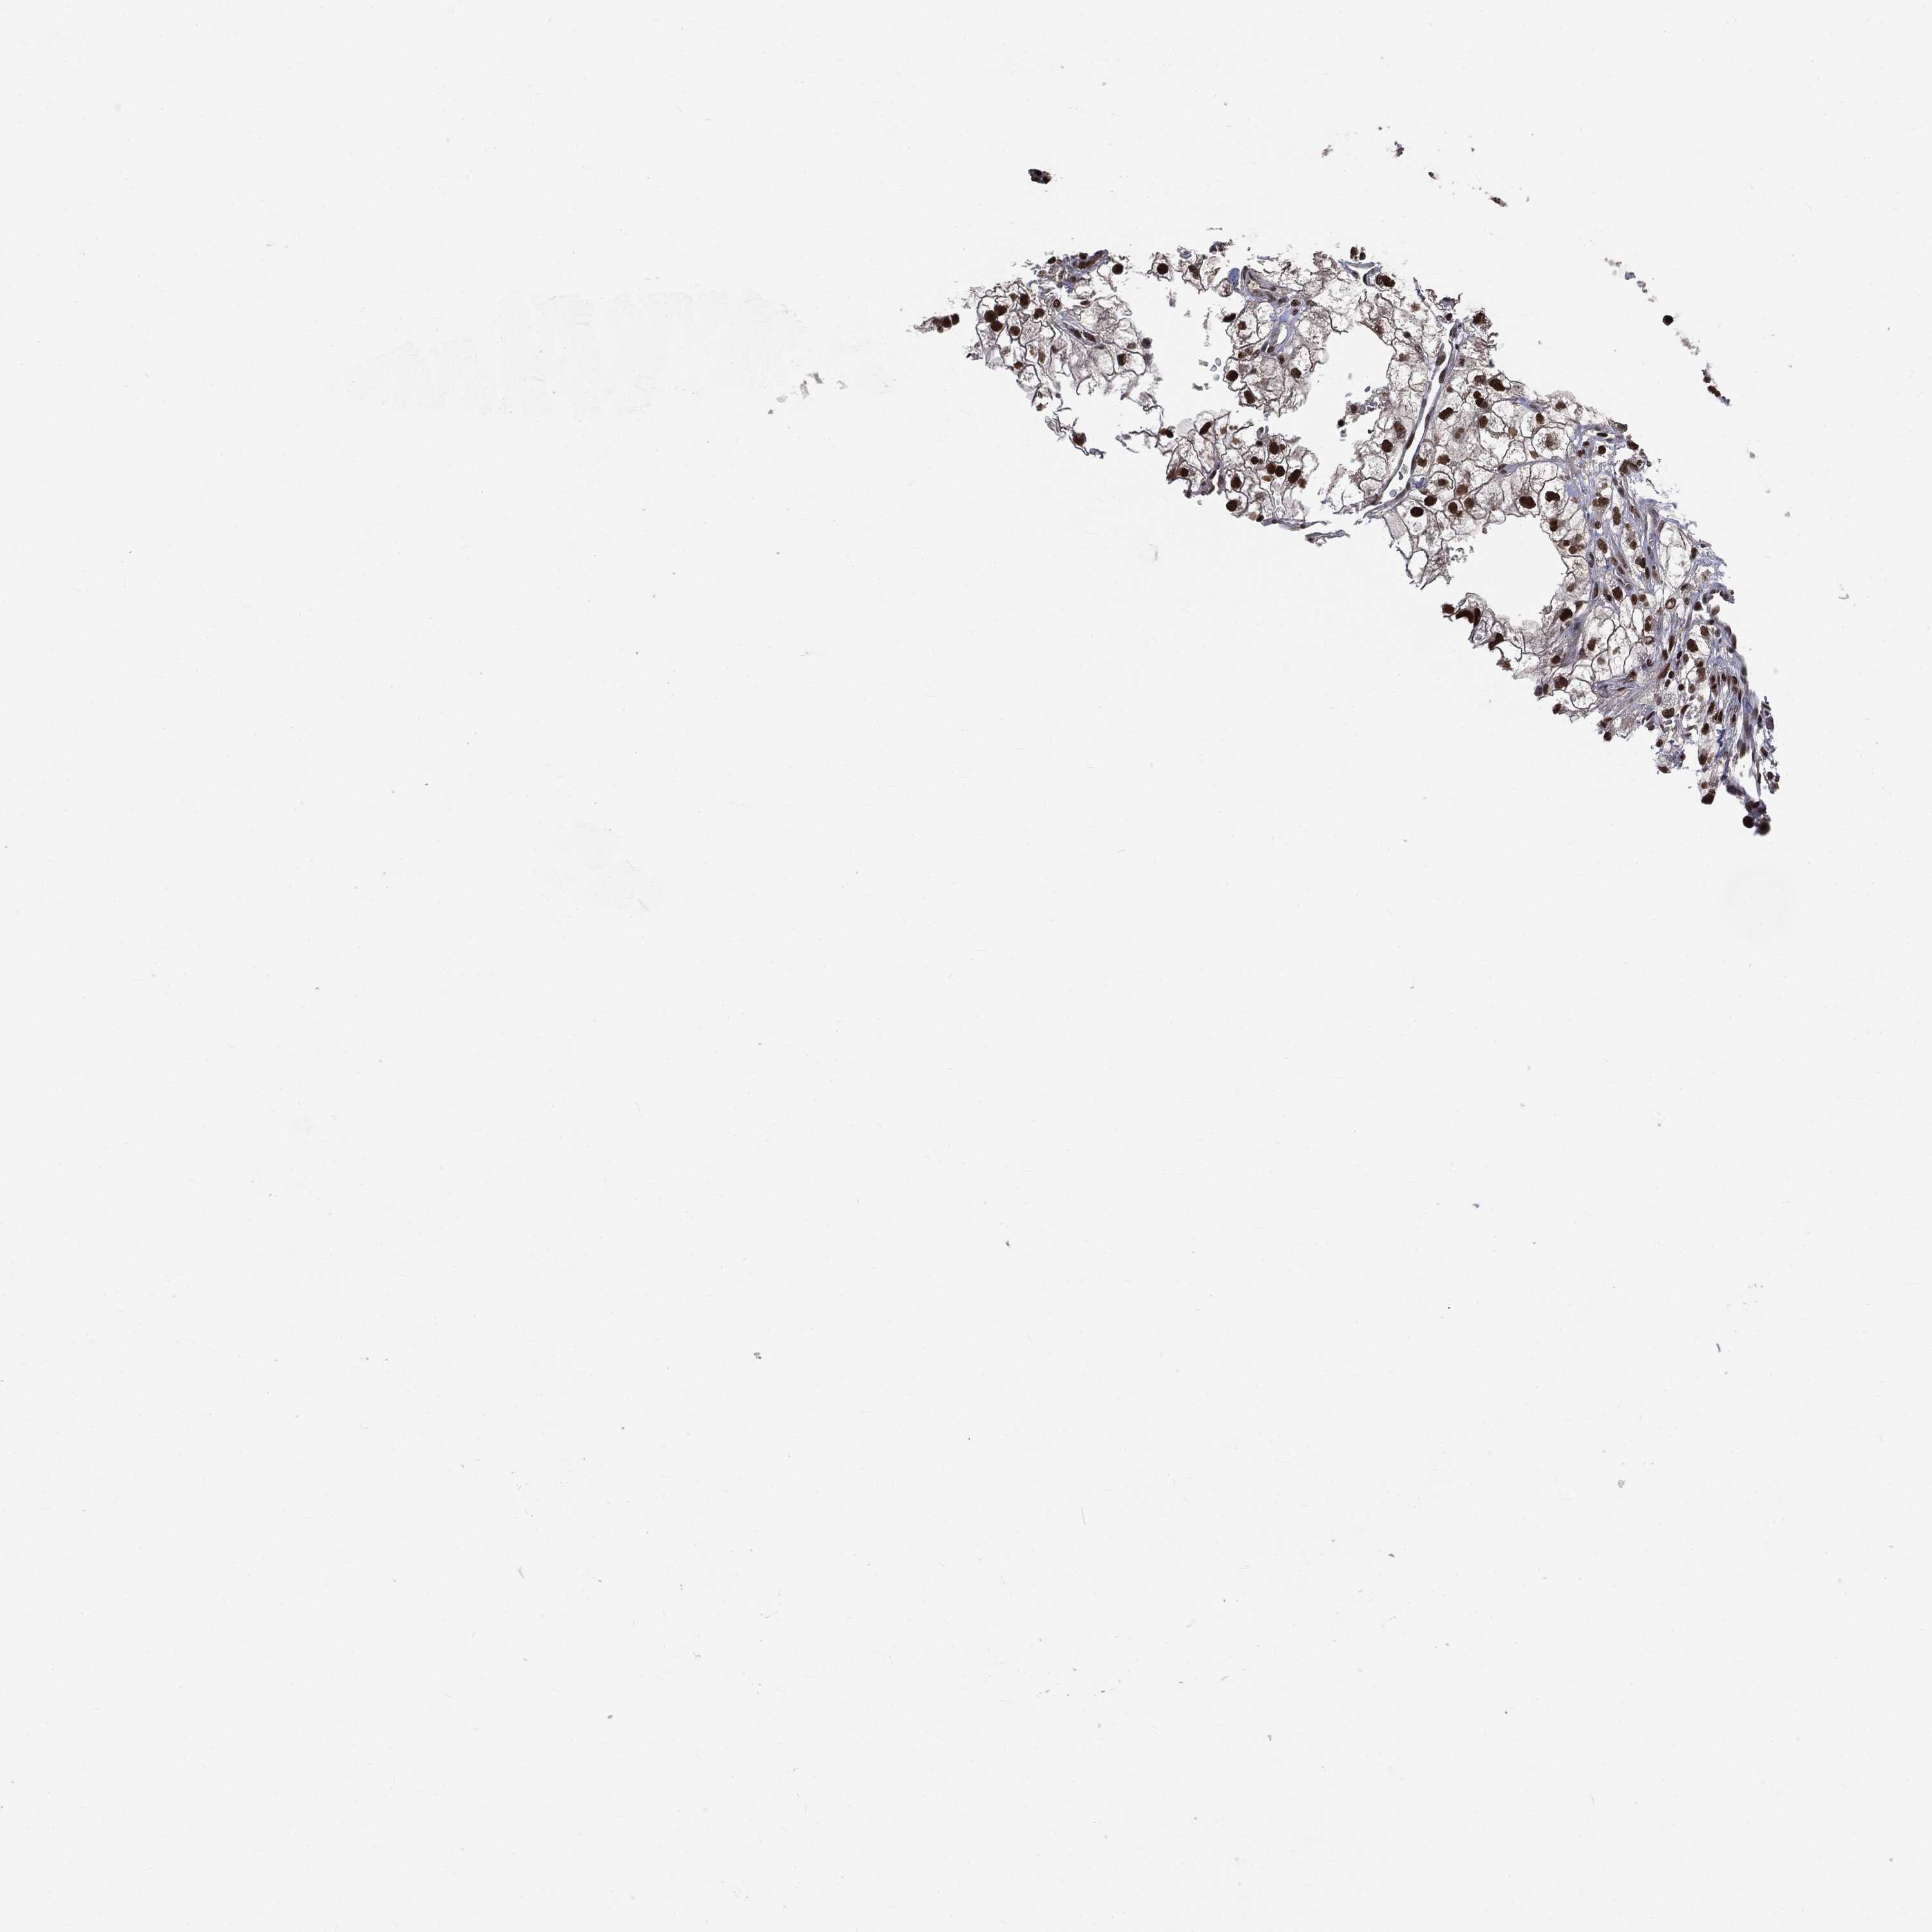

KIDNEY RENAL PAPILLARY CELL CARCINOMA (TCGA) - Interactive survival scatter ploti

The Survival Scatter plot shows the clinical status (i.e. dead or alive) for all individuals in the patient cohort, based on the same data that underlies the corresponding Kaplan-Meier plots. Patients that are alive at last time for follow-up are shown in blue and patients who have died during the study are shown in red.

The x-axis shows the expression levels (FPKM) of the investigated gene in the tumor tissue at the time of diagnosis. The y-axis shows the follow-up time after diagnosis (years). Both axes are complimented with kernel density curves demonstrating the data density over the axes. The top density plot shows the expression levels (FPKM) distribution among dead (red) and alive patients (blue). The right density plot shows the data density of the survived years of dead patients with high and low expression levels respectively, stratified using the cutoff indicated by the vertical dashed line through the Survival Scatter plot. This cutoff is automatically defined based on the FPKM cutoff that minimizes the p-score. The cutoff can be changed by dragging the vertical line or by entering a cutoff value in the square labeled "Current cut-off".

Under the Survival Scatter plot the p-score landscape (black curve; left axis) is shown together with dead median separation (red curve; right axis). Dead median separation is the difference in median mRNA expression between patients who have died with high and low expression, respectively. It is calculated as follows: median FPKM expression of dead patients with high expression - median FPKM expression of dead patients with low expression. This is intended to aid the user in visually exploring custom cutoffs and the associated p-scores and dead median separation.

Individual patient data is displayed and can be filtered by clicking on one or more of the category buttons on the top of the page. Categories describing expression level and patient information include: high, low, alive, dead, female, male and tumor stages. The scale of the x-axis can be toggled between linear and log-scale by clicking on the "x log" button. Mouse-over function shows TCGA ID, patient information and mRNA expression (FPKM) for each patient.

& Survival analysisi

Kaplan-Meier plots summarize results from analysis of correlation between mRNA expression level and patient survival. Patients were divided based on level of expression into one of the two groups "low" (under cut off) or "high" (over cut off). X-axis shows time for survival (years) and y-axis shows the probability of survival, where 1.0 corresponds to 100 percent.

DPH2 is not prognostic in Kidney Renal Papillary Cell Carcinoma (TCGA)

Best expression cut offi

Based on the FPKM value of each gene, patients were classified into two groups and association between prognosis (survival) and gene expression (FPKM) was examined. The best expression cut-off refers the FPKM value that yields maximal difference with regard to survival between the two groups at the lowest log-rank P-value. Best expression cut-off was selected based on survival analysis .